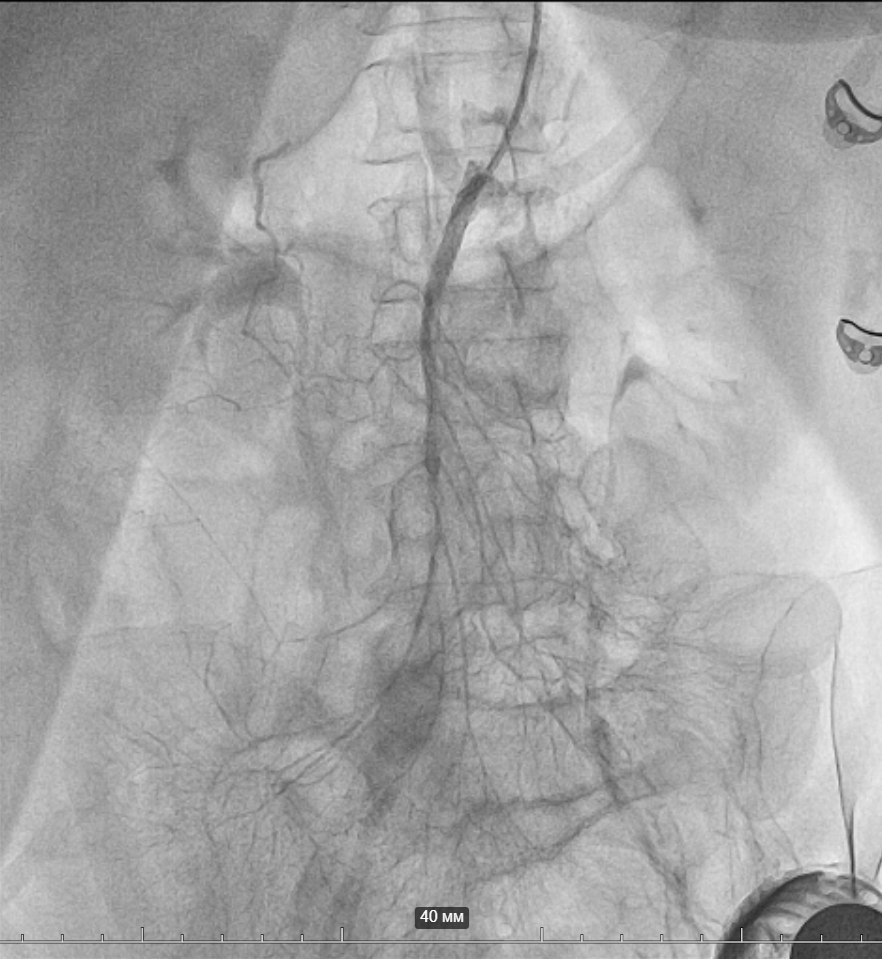

В январе к нам поступила пациентка в тяжелом состоянии: неделю страдала от болей в животе, рвотой и диареей. Компьютерная томография выявила тромбоз верхней брыжеечной артерии.

В ангиографическом кабинете врачи провели внутрисосудистую операцию — удалили тромб и установили 2 стента. Кровоток был успешно восстановлен, что позволило избежать сложную операцию с риском послеоперационных осложнений.